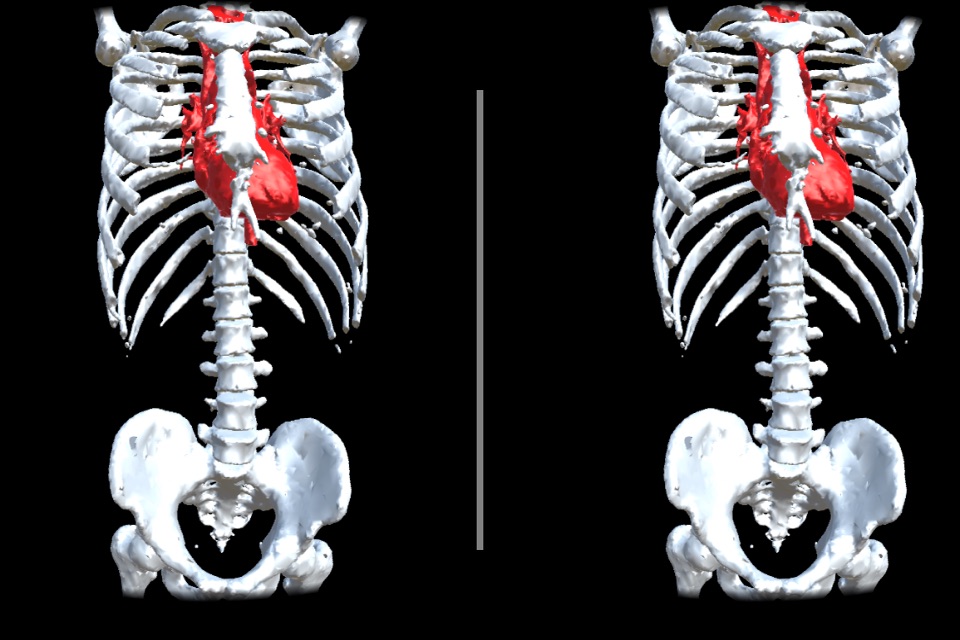

VR Body Guideは、まるで目の前にあるように、

人体の内部の様子をリアルに眺めて、

人体の不思議を楽しむことができる、医学教育用アプリです。

実際のCT画像から起こされた、本物の内臓のモデルを、間近に見ることができます

(これは似せて作られたモデルではありません!)。

・鑑賞するモデルは「頭部」と「胴体」の2種類です。

一方、胴体は、心臓、骨、皮膚をそれぞれON/OFFすることができます。